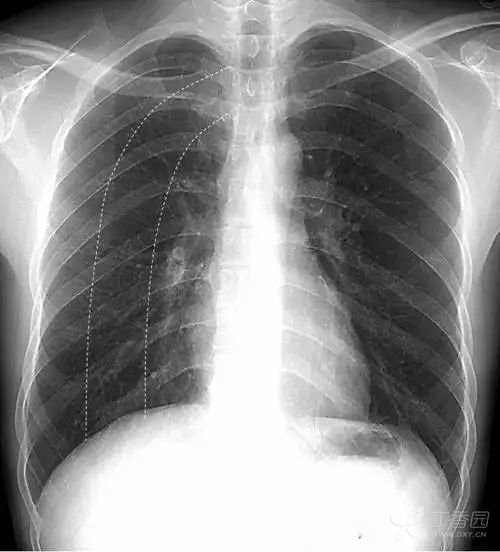

女性乳腺 女性乳腺相对胸部其他软策划较厚,因此在胸部正位X线平片上可以显示,通常重叠在两肺下野导致其密度增高,易被误认为肺内实变或肺内炎症。

上图女性乳腺影重叠在两肺下野,导致两肺下野对称性密度增高,乳腺形成投影的下缘(白色箭头)是清晰锐利的并且呈半圆形,常向外与腋部皮肤连续。没有乳腺重叠的两肺肋膈角区域更透亮。

鉴别:①两侧乳腺常规比较对称,所以在正位胸片上,乳腺重叠导致的两肺下野的密度增高也是比较对称的。而两肺下野均有病变且有分布比较对称的病理情况是比较少见的。②乳腺影的下缘清晰锐利且呈半圆形,向外与腋部皮肤连续。而肺内的病变不会延续到两肺以外。